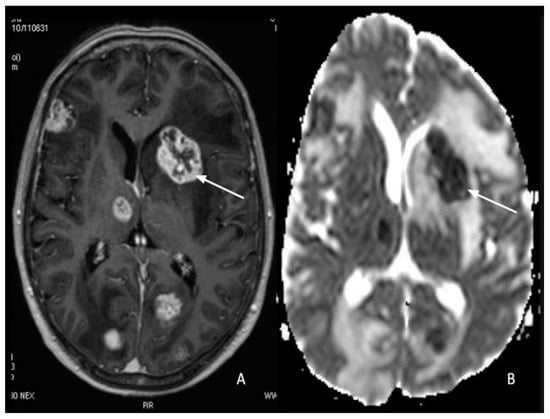

7. Metastasis

8. Gliomas vs. Metastasis